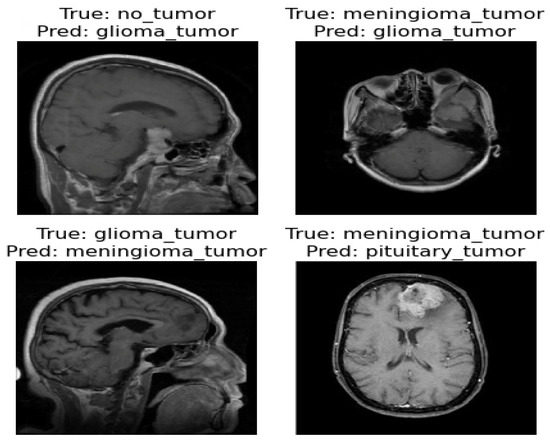

The confusion matrix was utilized to provide additional insights into the model’s performance by summarizing the correctly and incorrectly classified instances. For the validation set of 857 images, the model correctly identified 841 images, while 16 images were misclassified as shown in Figure 4. Furthermore, Figure 5 and Figure 6 present the classification outcomes of the proposed study, illustrating both accurate and inaccurate classifications.

Figure 6.

Incorrect classification result of proposed ViT model.

Figure 5 and Figure 6 present the visual results obtained from our FT-ViT model. These figures serve as compelling evidence of the model’s efficacy in accurately classifying different tumor types. As depicted in Figure 5, the proposed FT-ViT model exhibits remarkable performance, achieving an impressive accuracy of 98.13%. The high accuracy underscores the model’s capability to correctly identify tumor types with exceptional precision. However, there are instances where the FT-ViT model encounters challenges in accurately classifying tumor types. These instances are also reflected in the confusion matrix, which highlights the cases where the model misclassified tumor types. Figure 6 provides a visual representation of the results where the FT-ViT model encountered difficulties and failed to identify certain tumors accurately. The incorporation of both Figure 5 and Figure 6 allows us to comprehensively evaluate the FT-ViT model, highlighting its overall success in tumor classification, while also shedding light on areas for improvement.